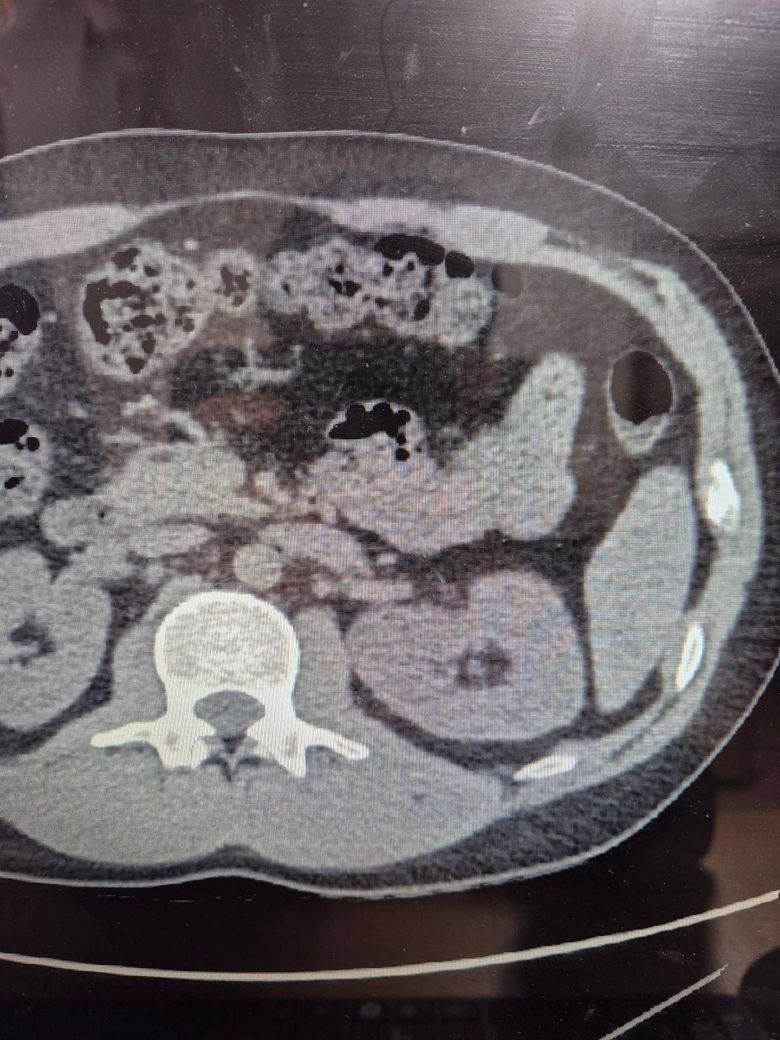

왼쪽 신장에 4.5센치 가량되는 혹이 있습니다.

맨처음은 가슴 시티상 2.5센치 가량되는 혹이였다고 했는데 복부 시티 결과 4.5센치 였습니다. 상급병원 기더리눈 동안 너무 불안해서요 ㅠㅠ 혹시 암일까요?

현재 4.5cm 정도의 신장 종괴가 있는데, 이 크기면 양성도 있고 악성도 있을 수 있어서 정밀평가가 필요합니다.

현재 올려주신 사진을 바탕으로는 암인지 아닌지 알기 힘듭니다.

신장 혹이 암인지 아닌지는 CT만으로 판단이 완전하지 않습니다.(사진도 충분하지 않습니다. )

좌측

사진 상으로는 내부가 균질해 보이는 듯하지만 CT 화질만으로 양성/악성을 단정할 수는 없습니다.

그러나 크기가 4cm를 넘기 때문에 반드시 평가를 받아야 합니다.

다만 급성 위험이 느껴지는 형태는 아니므로 진료 대기하는 동안 미리 너무 걱정하지는 않으셔도 됩니다.